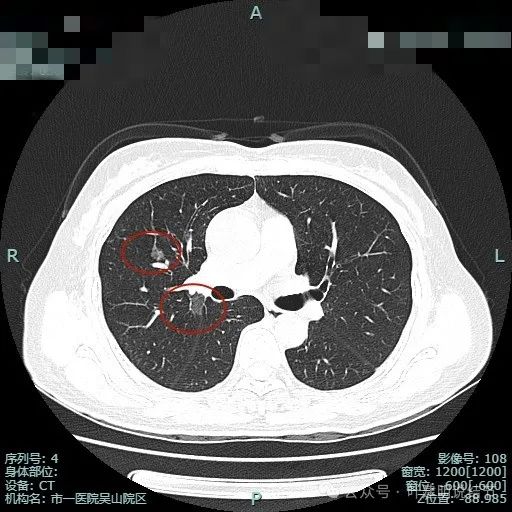

左下叶背段病灶出现(病灶1),靠叶间裂,密度不纯,若单此层当然并不一定是恶性,也可能是慢性炎的。

胸膜似略有牵拉密度不纯。

出现小空泡征以及偏实性成分,并有淡磨玻璃成分,整体轮廓较清,瘤肺边界较为清楚。

叶间胸膜有牵拉,病灶内部密度欠均匀。表面有浅分叶征。